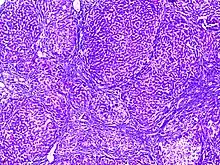

![]() | Diffuse B-cell lymphoma | Lymph node FNA specimen showing diffuse large B cell lymphoma. | Category: Histopathology of diffuse large B cell lymphoma | Diffuse large B-cell lymphoma |

![]() | Follicular lymphoma | Micrograph showing a small B-cell lymphoma compatible with follicular lymphoma. H&E stain. | Category: Histopathology of follicular lymphoma | Follicular lymphoma |